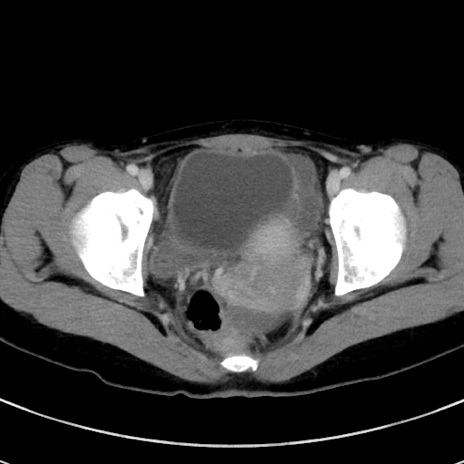

症例17(横断像)

【症例】20歳代女性

【主訴】嘔吐、下腹部痛

【現病歴】昨日夕食後に嘔吐し下腹部痛が出現。本日になっても嘔吐持続し改善しないため来院。

【身体所見】意識清明、BT 37.2℃、BP 108/67mmHg、腹部:平坦、やや硬、下腹部正中から右にかけて圧痛あり、反跳痛軽度あり、tapping pain(+)。

【データ】WBC 13600、CRP 14.94